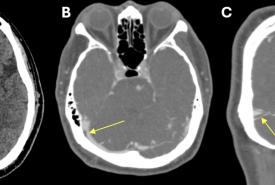

Homonymous Hemianopia Associated with COVID-19 Vaccination